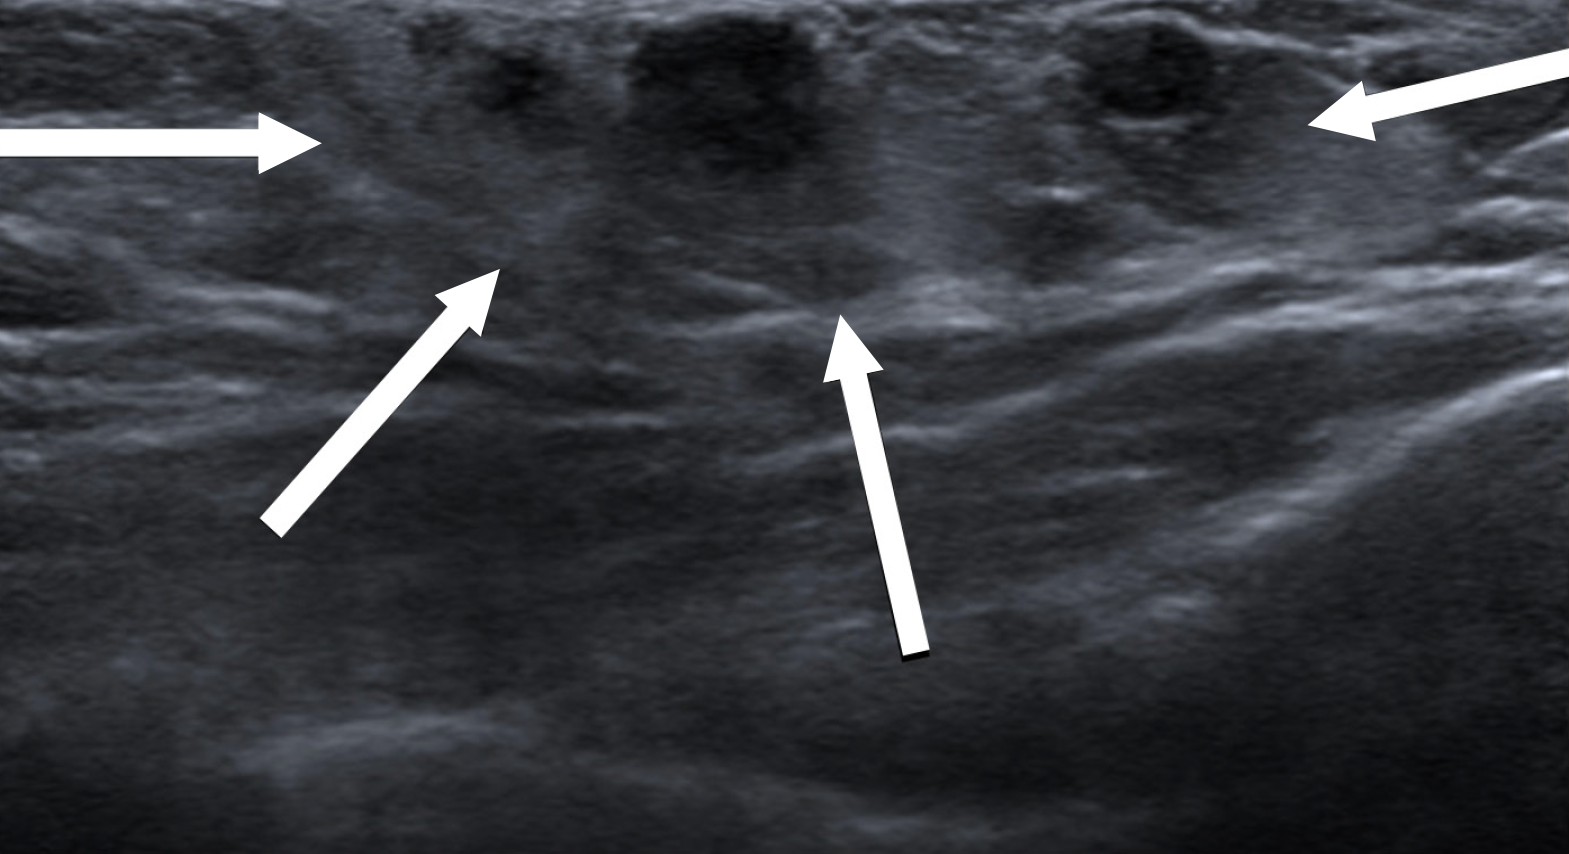

Figure 6 Diffuse gynecomastia in a 42-year-old male on estrogen therapy.

A: Mediolateral oblique; B: Craniocaudal mammography images showing a diffuse increase in breast density, with the male breast resembling the female breast; C and D: Ultrasound images showing diffuse deposition of glandular tissue (white arrows).